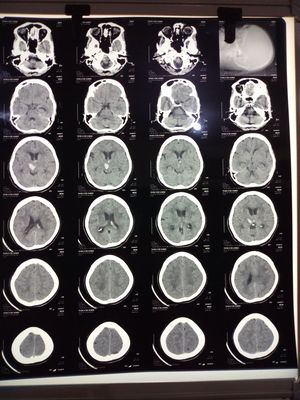

Whats wrong with this ct

of hemiplegia